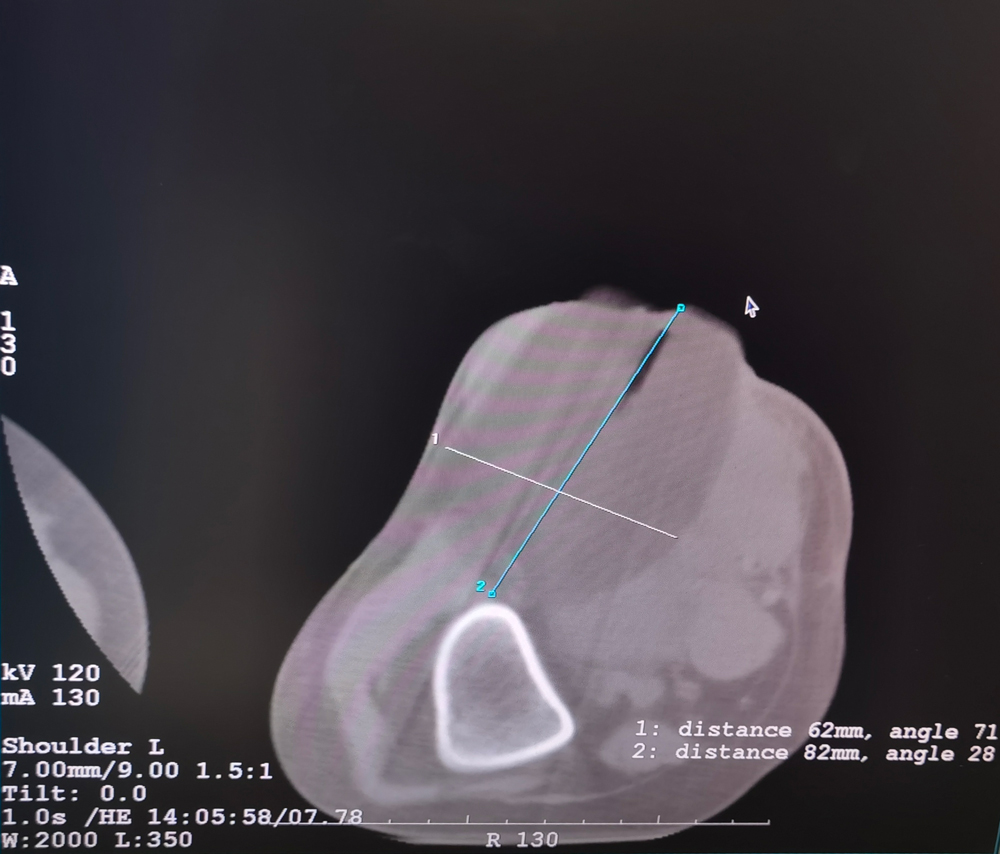

女,42歲,復發(fā)性脂肪瘤,病灶位于右側膝關(guān)節,直徑大小13cm。采用雙針?lè )桨?,共進(jìn)行6個(gè)凍融循環(huán),最大冰球直徑達8.2cm,術(shù)中多方位治療全面覆蓋病灶范圍。患者術(shù)后狀況良好。